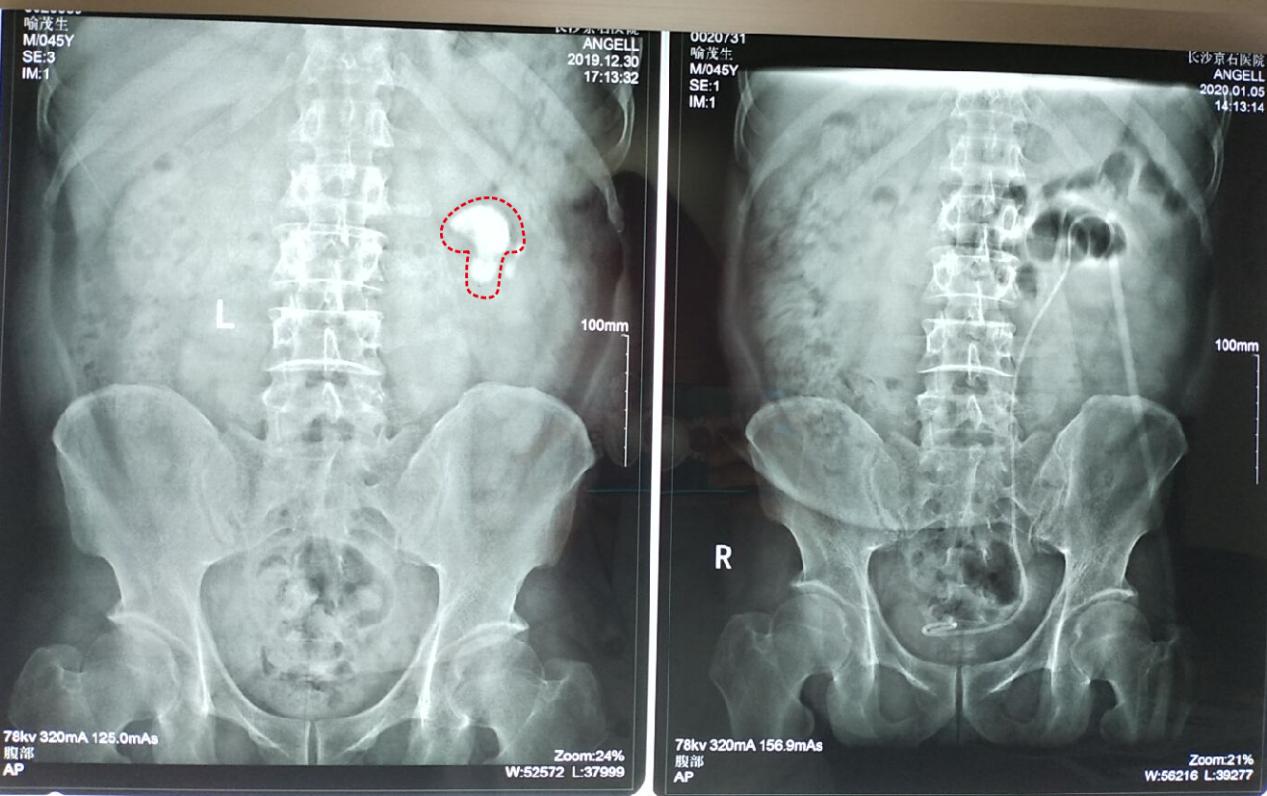

46岁的喻先生在益阳从事瓷砖销售生意,近两年在装卸瓷砖时明显感觉腰部不能受力,且腰痛现象也越来越频繁,严重影响了他的日常工作和生活,为此喻先生前往当地医院检查,结果发现左肾有结石并积水,并且最大的一枚结石形似一朵“蘑菇”,当地医生建议尽快手术治疗。

原来早在2012年喻先生就患有肾结石和输尿管下端结石,当时通过体外碎石将输尿管下段结石清除干净,但由于体外碎石针对肾脏结石会有危险,就没有将肾结石清除,这些年一直靠服用排石药物坚持保守治疗。

近日,喻先生来到长沙京石结石病医院进行就诊。由于结石较大无法单独使用纤维肾镜,为了保证在最大化清除结石的同时又能保护肾脏,湖南医声特约权威专家——长沙京石结石病医院泌尿结石科主任张明忠为他制定了双镜联合微创保肾取石术治疗方案。1月2日,手术成功实施,喻先生现已康复出院。